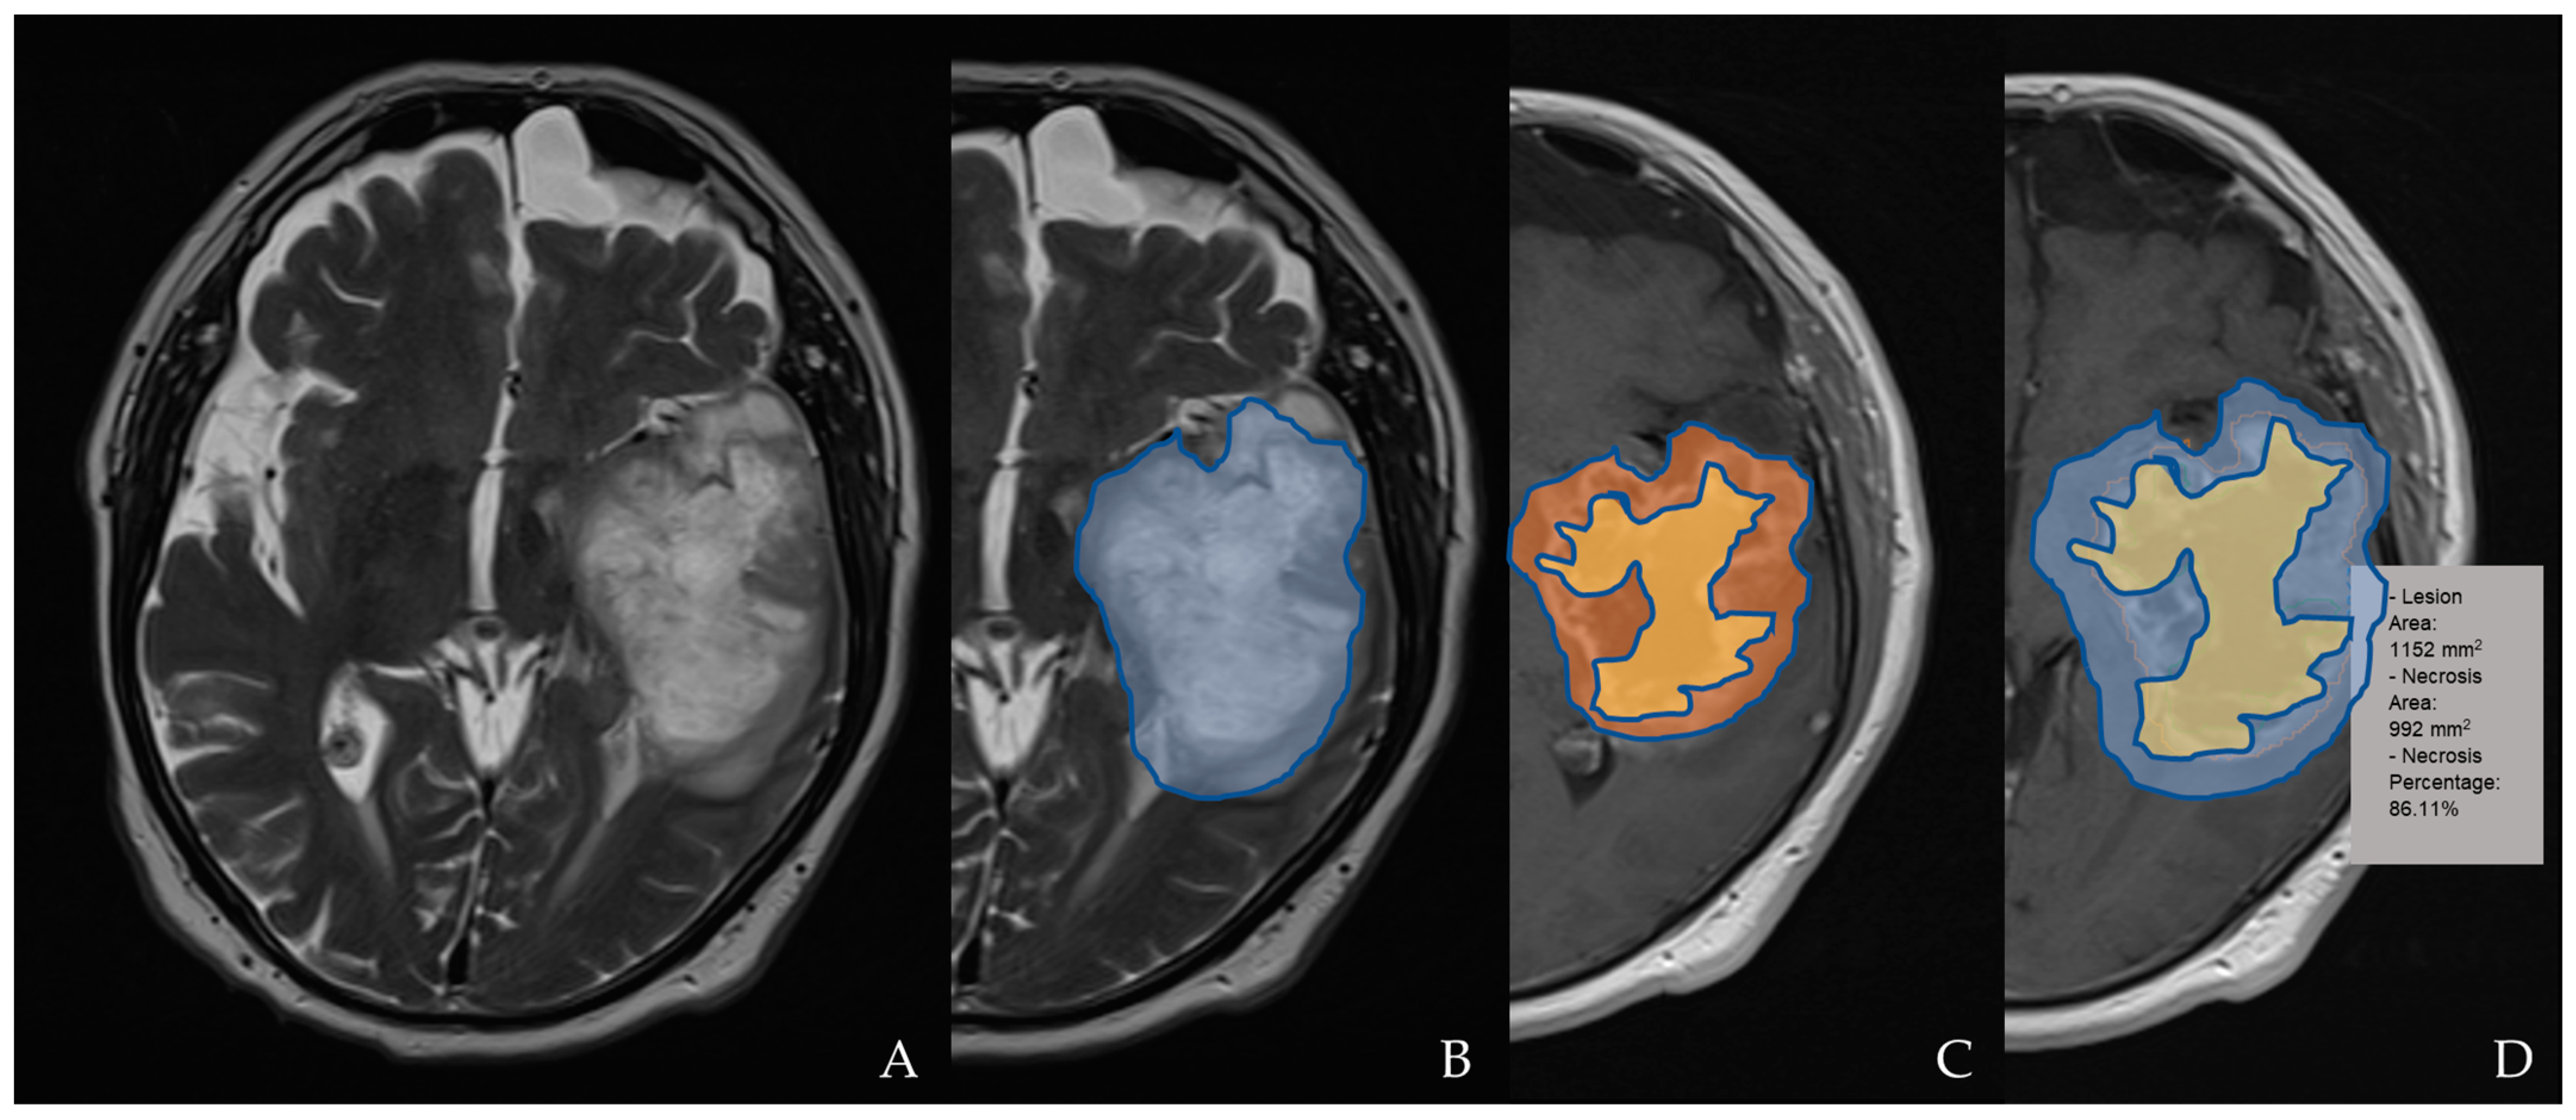

2.4. Magnetic Resonance Imaging Assessment and Analysis